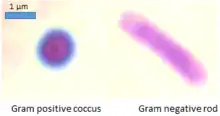

Gram stain (Gram staining or Gram's method), is a method of staining used to classify bacterial species into two large groups: gram-positive bacteria and gram-negative bacteria. It may also be used to diagnose a fungal infection.[1] The name comes from the Danish bacteriologist Hans Christian Gram, who developed the technique in 1884.[2]

Gram staining differentiates bacteria by the chemical and physical properties of their cell walls. Gram-positive cells have a thick layer of peptidoglycan in the cell wall that retains the primary stain, crystal violet. Gram-negative cells have a thinner peptidoglycan layer that allows the crystal violet to wash out on addition of ethanol. They are stained pink or red by the counterstain,[3] commonly safranin or fuchsine. Lugol's iodine solution is always added after addition of crystal violet to strengthen the bonds of the stain with the cell membrane.

Gram-positive bacteria have a thick mesh-like cell wall made of peptidoglycan (50–90% of cell envelope), and as a result are stained purple by crystal violet, whereas gram-negative bacteria have a thinner layer (10% of cell envelope), so do not retain the purple stain and are counter-stained pink by safranin. There are four basic steps of the Gram stain:

After decolorization, the gram-positive cell remains purple and the gram-negative cell loses its purple color.[17] Counterstain, which is usually positively charged safranin or basic fuchsine, is applied last to give decolorized gram-negative bacteria a pink or red color.[3][18] Both gram-positive bacteria and gram-negative bacteria pick up the counterstain. The counterstain, however, is unseen on gram-positive bacteria because of the darker crystal violet stain.